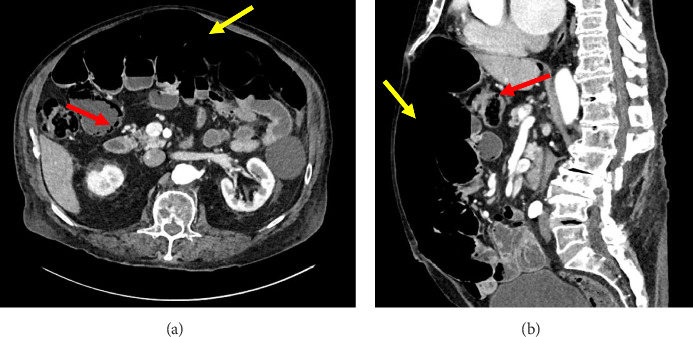

We present our experience with a patient with acute-on-chronic asymptomatic pneumoperitoneum with spontaneously resolving idiopathic pneumatosis intestinalis that was solely managed on close observation alone. This case is unique in that it details the approach to nonoperative management of massive free air under the diaphragm identified incidentally on routine preventative health screening and longitudinal follow-up over an 8-month period. In the absence of known and underlying systemic disease, efficient and coordinated clinical work-up and evaluation for comorbid diagnoses associated with pneumoperitoneum can serve to guide management and avoid unnecessary surgery for stable and asymptomatic patients.